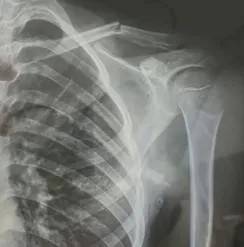

10月23日,内蒙古赤峰市宁城县苏木皋小学一学生被老师打伤致锁骨骨折三角货币对冲指标。10月31日,家长贾女士给生活报记者打来电话称,事件已经过去一周时间了,但是校方还没有到医院给孩子道歉,且涉事教师还在上班。

10月30日,内蒙古自治区赤峰市宁城县苏木皋小学一学生家长贾女士给记者打来电话,介绍了孩子被打的原因三角货币对冲指标。贾女士称,放学通道的墙上有一个电灯的开关,好多孩子放学时都随手去拨弄开关。出于安全考虑,学校和老师都禁止孩子拨弄开关。23日放学时,他儿子和另一个同学调皮,再去拨弄了那个开关,被正在值班的另一个班的班主任发现,把她儿子打了,且打骨折了。

图片由报料者提供